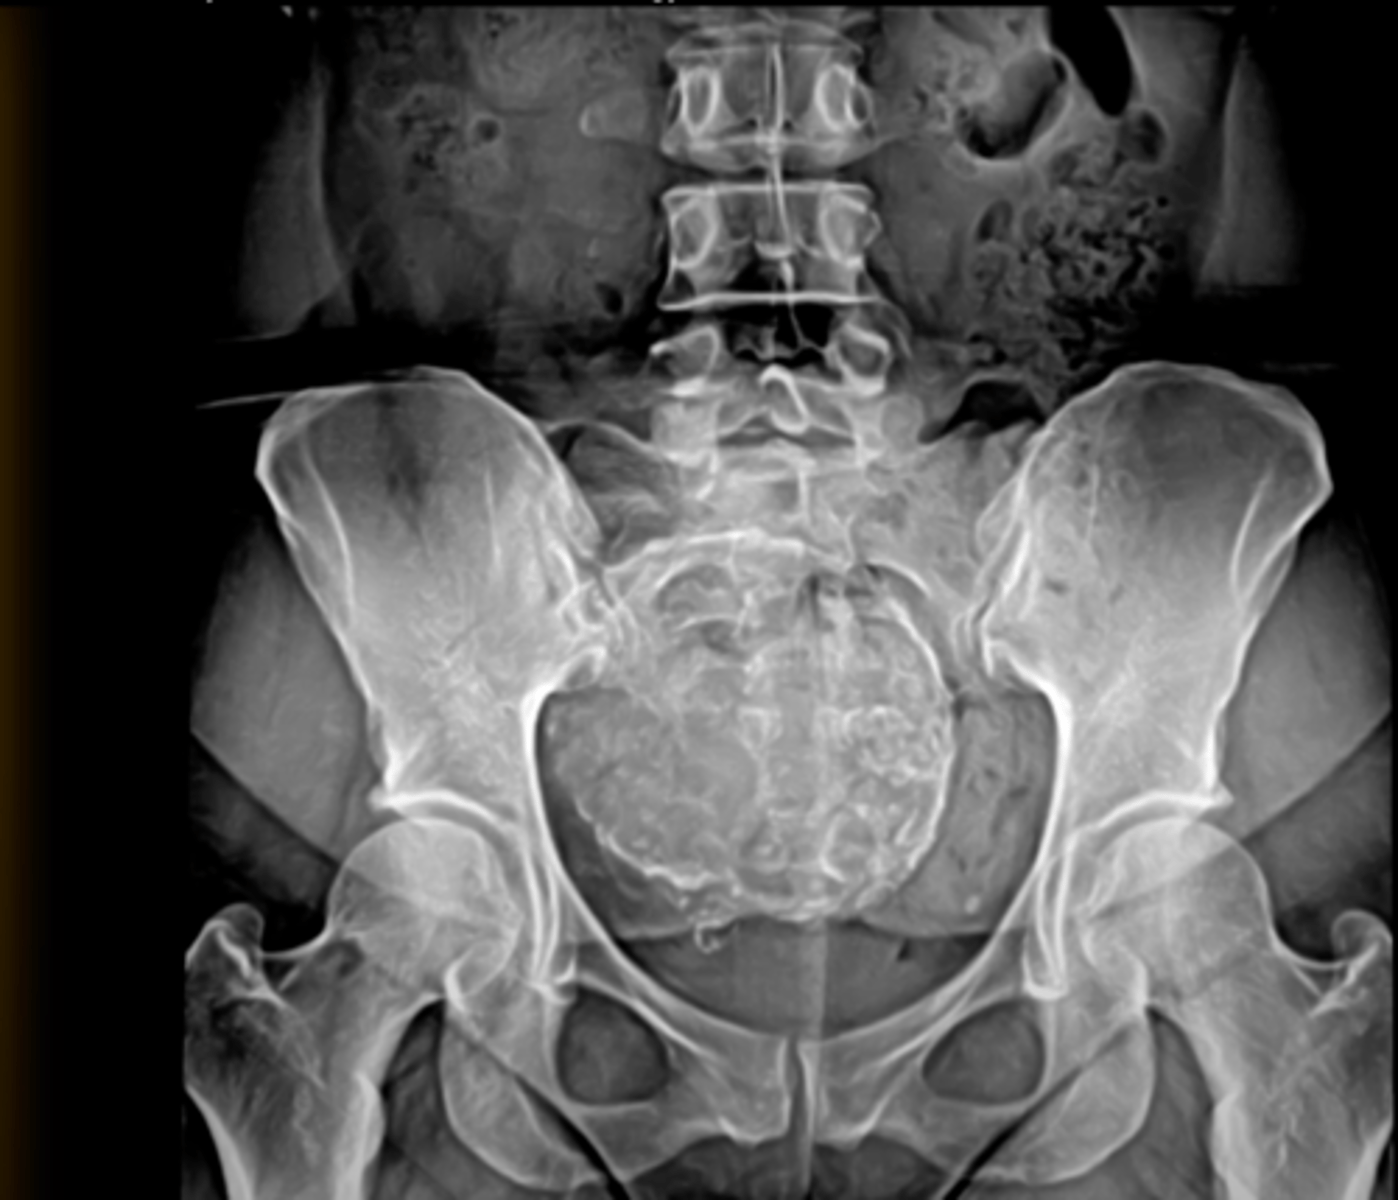

Fibroid

Phleboliths (venous calcifications)

Uterine fibroid/Leiomyoma